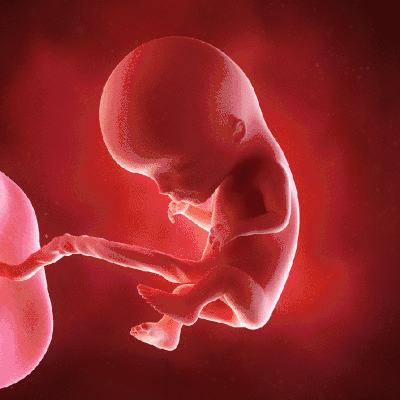

准确地说,现在的我还只是一个胚芽。我在你的身体里飞快地长,成功地长出了三胚层。三胚层将来会长成我身体的不同部分,作为“成长核心”。

宝贝在自己的房子里拼命地生长:我的心脏开始有规律的跳动,并且开始供血。我的心跳达到150次/分钟,相当于大人们心跳的两倍,心脏也化分为左心房和右心室。

连接脑和脊髓的神经管开始工作;我的四肢、五官等都已经开始有了雏形。

妈妈,在我们共同的努力下,现在的我已经打好了未来成长的基础!以前的小尾巴不见了;所有的神经肌肉器官都开始工作了。

四肢也开始长出来了;骨头也越长越硬了;已经开始在“小房”里做小运动了;还有,现在我知道自己是男孩子还是女孩子了。

目前我们已经进入了脑迅速增长期,我的脑细胞体积增大和神经纤维增长,使脑的重量不断增加,要想让我长成一个聪明的宝宝,现在可是关键时刻!

妈妈,现在的我不仅越来越壮实,还越来越有模有样了呢!我的身上开始长了一层小绒毛,头发也长成来了;还有我做鬼脸,斜着眼睛,有时候吸手指。

科学家们说,这些动作都可以促进大脑的成长。有一天我打了一个嗝,当然,那声音太小,你肯定没听见。

里面的生活虽然单调,又漆黑黑的一片,但我很快就找了一样新玩具那就是脐带。我会拉它,用手抓它,你不必太担心,我会很有分寸的对待它的,我知道那是我空气和养分的来源,也是与你交流的主通道。

大脑细胞迅速增殖分化,体积增大,妈妈,你得多吃一些健脑的东西来帮帮我。我的大脑皮层表面开始出现特有的沟回,脑组织快速的增长。甚至长出了头发。